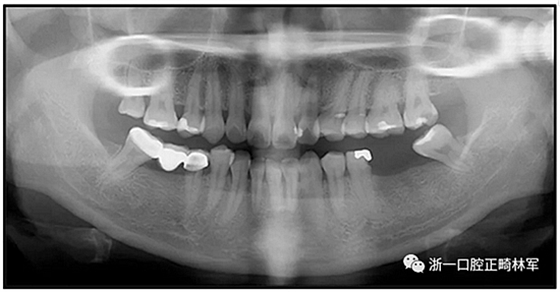

36歲;女性;尋求下頜左后方區(qū)域間隙管理的建議(圖1和圖2),通過(guò)治療獲得了良好的牙頜面效果(圖3和圖4)。她被診斷患有骨性I類和代償性牙性II類錯(cuò)合畸形,并且上頜左側(cè)尖牙缺失(圖1和2)。大約七年前,由于不可修復(fù)的齲齒,拔除了下頜左側(cè)第一和第二磨牙(圖5)。37相鄰的第三磨牙向近中移動(dòng)并傾斜入間隙,導(dǎo)致無(wú)牙頜間隙減小至約14 mm(圖2和圖5)。臨床和影像學(xué)評(píng)估顯示多發(fā)性齲損和在下頜右側(cè)567處有一不良的固定橋修復(fù)體(圖1和5)。此外,下頜左中切牙缺失,造成下頜中線向左側(cè)偏移約3 mm(圖1和圖2)?;颊咦栽V,她的右上第一前磨牙和左上尖牙在13歲時(shí)由其家庭牙醫(yī)拔除,因?yàn)樗鼈儽蛔枞筋a側(cè)萌出(圖1)。上頜第二磨牙缺失(未知病因),并且相鄰的第三磨牙已經(jīng)轉(zhuǎn)移到第二磨牙間隙中。如補(bǔ)充材料所示,美國(guó)正畸學(xué)差異指數(shù)DI是28分。種植體部位(下頜左側(cè)和右側(cè)第一磨牙)由于復(fù)雜性得到額外4分(補(bǔ)充材料)。

圖5. 治療前的側(cè)位片(上圖)和全景(下圖)的X光片